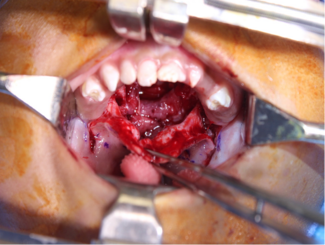

Katherine C. Benedict, MD; Brittany N. Corder, BS; Ian C. Hoppe, MD, BA; Kathryn W. Brown, MD

The authors present a new method for closure of a wide Veau class II cleft palate in which anterior palatal closure was achieved by use of a bipedicled mucoperiosteal anterior palatal flap.